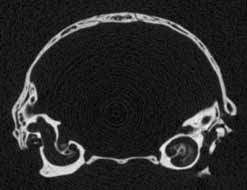

Several features of mammalian development are visible in members of the growth series shown on this website. An obvious change is the thickening of the skull elements as ontogeny progresses -- particularly the bones that surround the braincase and the ear region (contrast the thickness of the bones in the unreduced coronal slice #401 in day 27 and the unreduced coronal slice #390 in day 90, shown below). A feature associated with the thickening of the skull bones is the closure of the parietal fontenelle between days 48 and 57.

Reduced coronal slice #390 through the braincase of day 90 specimen. Click on the thumbnail for an unreduced version. |